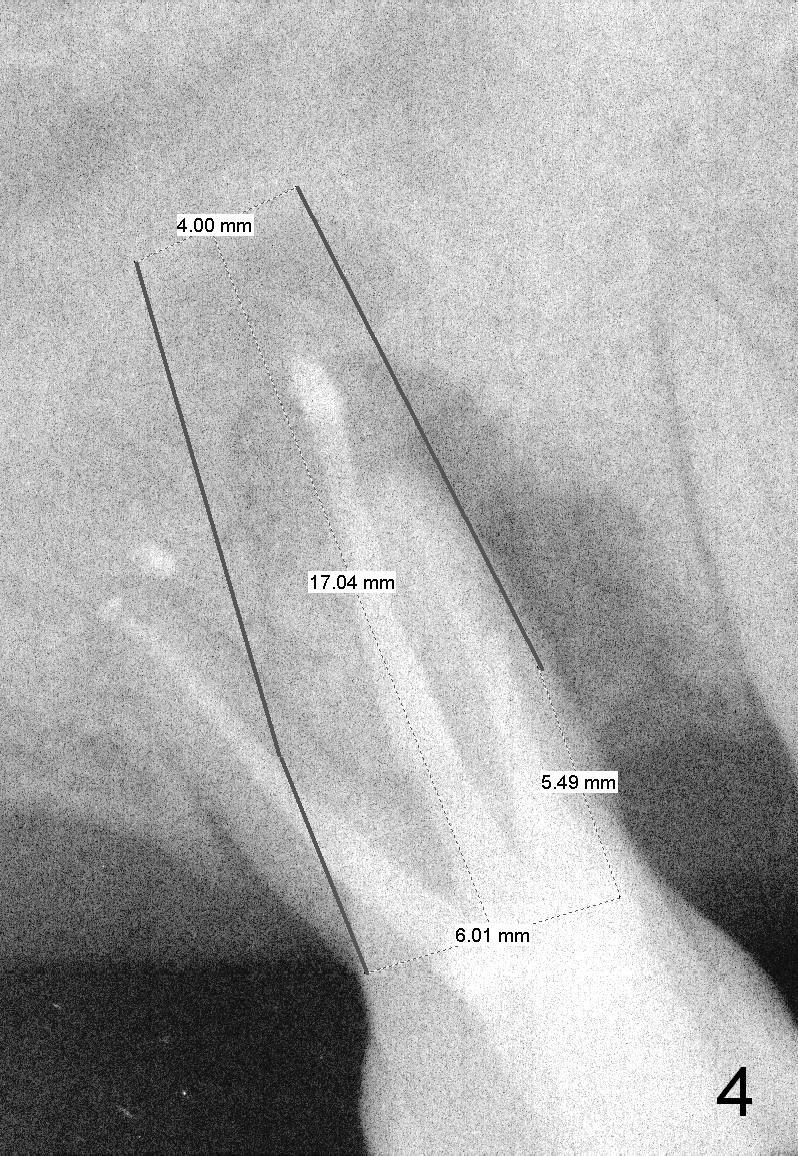

Two years post RCT, there is radiolucency around the MB root of the tooth #3 (Fig.1,2). Eleven days later, there is acute infection associated with MB and DB root fracture (Fig.3). According to the X-ray taken 11 days earlier (Fig.1,4), a long tissue-level implant (6x17 mm) is suitable for the site. In accordance with CBCT (coronal (Fig.5) and sagittal (Fig.6) sections) taken prior to RCT, a short bone-level implant (6.9x10 mm) is a more reasonable choice.

After extraction, the socket will be studied to determine where the bone is and where bony defects are for the site of the initial osteotomy. Start with 2 mm pilot drill or RT2, apparently ~ 6 mm depth, followed by reamers 2.5-3.5 mm and Tatum taps 4.5-7x17 mm (14 mm depth from gingival margin). Use a latch adapt with the torque wrench. Due to severe bone loss, the tap should not be too large (6 mm). If insertion torque is high and bone morphology is favorable, change to DIO taps and take necessary PAs to decide the length of the implant relative to the sinus floor and trajectory. If the depth is 10 mm or less, use SM; 12 mm UF. Based upon the most recent X-ray (Fig.3 with large lesion), the implant should be large and long (Fig.7: 7x17 mm).